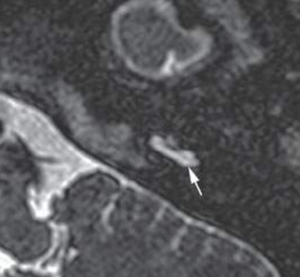

Manyetik rezonans görüntüleme (MR). Bu test, vücudunuzun içindeki ayrıntılı görüntüleri yakalamak için radyo dalgaları ve güçlü mıknatıslar kullanır. Felç durumunu dışlamak için MR yararlıdır (Şekil 1).

Şekil 1. İç kulak iltihabı, yani labirentit olan bir kulakta MR görüntüsü. Ok işareti işitme organı olan kokleayı (salyangoz) işaret etmektedir.